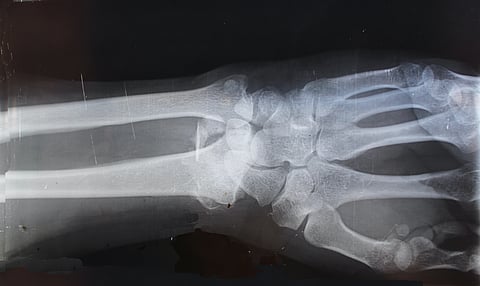

Osteoarthritis is the most common form, involving degeneration of joints, often in the hands, hips, and knees. RA is less common, but still affects more than two million Americans, primarily women. It is a systemic autoimmune disease characterized by long-lasting or chronic, painful tissue inflammation in affected joints. It can also cause problems in other organs, such as the lungs, heart, and eyes.